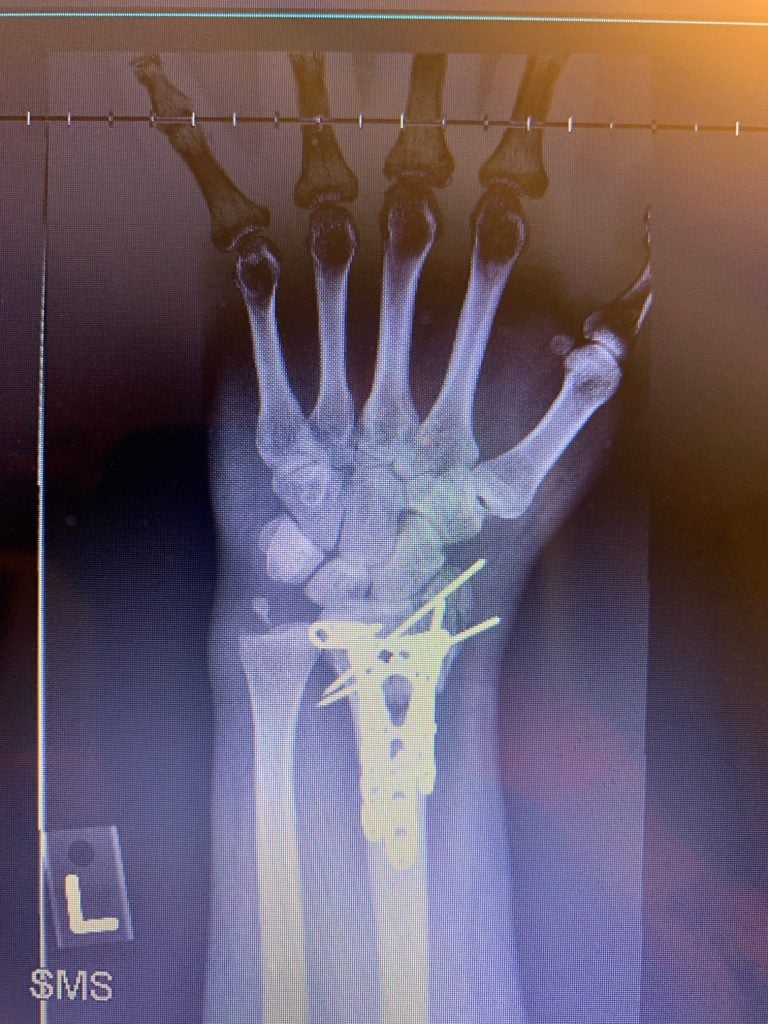

It all happened in a flash: I was biking on a warm Friday afternoon before Labor Day and all of a sudden I hit a pothole. I found myself lying in the street in agonizing pain with my left wrist tremendously swollen. At the emergency room, the doctors set my wrist somewhat in place and placed me in a cast up to my bicep. But they told me that I needed to have my wrist examined very soon (see photos 1, 2 and 3).

In the recovery room after surgery, Dr. Daluiski said that everything went well, even though it was a very severe accident. He inserted multiple plates and screws to help set my wrist (see photo 4). It was pretty painful for 2-3 days after surgery, but after that my wrist began to feel progressively better. I saw Dr. Daluiski about one week after the surgery and he said everything looked great so far (see photo 5 and 6). I was amazed that my wrist began to look like a normal wrist and that I was able to begin performing gentle range of motion exercises with the occupational therapists at the hospital. About six weeks after the surgery, I had a second surgery to remove some of the hardware in my wrist. The second surgery also went very smoothly. Throughout this process, I continued working with the occupational therapists to regain the motion and strength in my wrist.